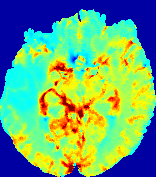

Figure 4: PIANO feature maps for another patient in the ISLES 2017 training set, where the lesion is located in the right hemisphere. Top row: segmented stroke lesion region (white) on different slices. The corresponding slices for the PIANO feature maps are shown in the following rows.

For a better insight into an estimated velocity field 𝐕𝐕{\bf{V}} and diffusion field 𝐃𝐃{\bf{D}}, we compute the following maps: (1) 𝐕rgbsubscript𝐕𝑟𝑔𝑏{\bf{V}}_{rgb}: Color-coded orientation map of 𝐕=(Vx,Vy,Vz)T𝐕superscriptsuperscript𝑉𝑥superscript𝑉𝑦superscript𝑉𝑧𝑇{\bf{V}}=(V^{x},V^{y},V^{z})^{T}, obtained by normalizing 𝐕𝐕{\bf{V}} to unit length and mapping its 3 components to red, green, blue respectively; (2) 𝐕2subscriptnorm𝐕2\|{\bf{V}}\|_{2}: 222 norm of 𝐕𝐕{\bf{V}}; (3) D𝐷D: scalar field in Eq. 5.

Fig. 3 and Fig. 4 show the PIANO feature maps estimated from two ISLES 2017 patients: all are highly consistent with the lesion in both cases. Details of the blood flow trajectories are revealed in 𝐕rgbsubscript𝐕𝑟𝑔𝑏{\bf{V}}_{rgb} by the ridged patterns and the sharp changes of colors in the unaffected (right) hemisphere, while the flat patterns appearing within the lesion provide little directional information about the velocity and indicate low velocity magnitudes. Velocity magnitudes are more directly visualized via 𝐕2subscriptnorm𝐕2\|{\bf{V}}\|_{2}, from which one can easily locate the lesion where 𝐕2subscriptnorm𝐕2\|{\bf{V}}\|_{2} is low. D𝐷D also indicates lower diffusion values in the lesion, though with less contrast potentially due to the fact that it captures the accumulated effect of CA diffusion at the voxel-level.